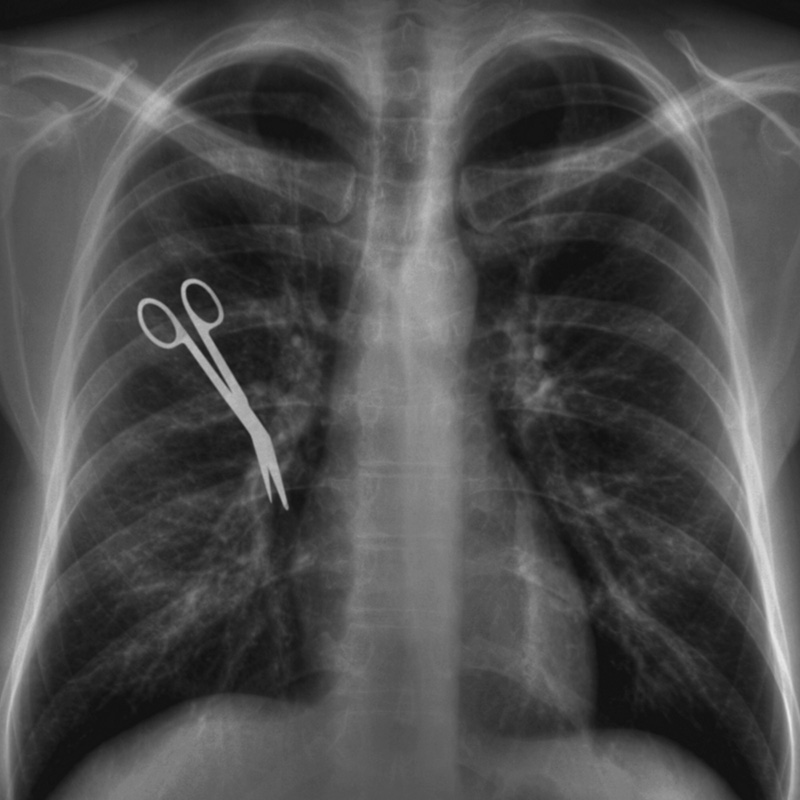

Em determinados momentos, a impressão é que a coisa menos importante dentro de um hospital é o doente. A cada hora, pelo menos três pacientes sofrem algum incidente em unidades de saúde do Brasil. São vítimas de erros grotescos, verdadeiras trapalhadas, que, muitas vezes, são fatais. Episódios que beiram o absurdo, como o misterioso desaparecimento do corpo de um bebê em um hospital do Méier, fazem parte da série de aberrações. Essas falhas, que poderiam ser evitadas, são classificadas como Eventos Adversos (EA) e Never Events (NE), erros graves que nunca deveriam ocorrer em serviços de saúde. Casos bizarros, como esquecer material hospitalar dentro do paciente após a cirurgia, operar o lado errado do corpo ou até o paciente errado, constam na lista de EA e NE da Agência de Vigilância Sanitária (Anvisa).

O mais recente levantamento da Anvisa, com base nas notificações feitas pelos 1.372 Núcleos de Segurança do Paciente (NSP) do país, relata 796 NE, com 16 óbitos, em 2015. Os EA atingiram 31.774 casos nos serviços de saúde pública e privada do Brasil. Os números assombrosos da Anvisa estão longe de retratar a realidade, que é muito mais grave, já que a praxe é ocultar os casos.